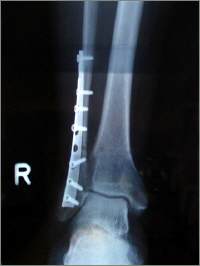

... legte ich mich ins Bett, damit die Verstauchungsschmerzen nachlassen. Als es am anderen Morgen noch immer schmerzte, brachte mich Vreni zum Hausarzt, zum röntgen. Und anschliessend gleich ins Spital, das Wadenbein war gebrochen. Inzwischen war das Bein so angeschwollen, dass mit der Operation ein paar Tage gewartet werden musste. Titanblech, Schrauben, Gips. Wobei der Gips längst nicht mehr aus Gips ist, sondern aus 2-Komponenten Kunststoff. |